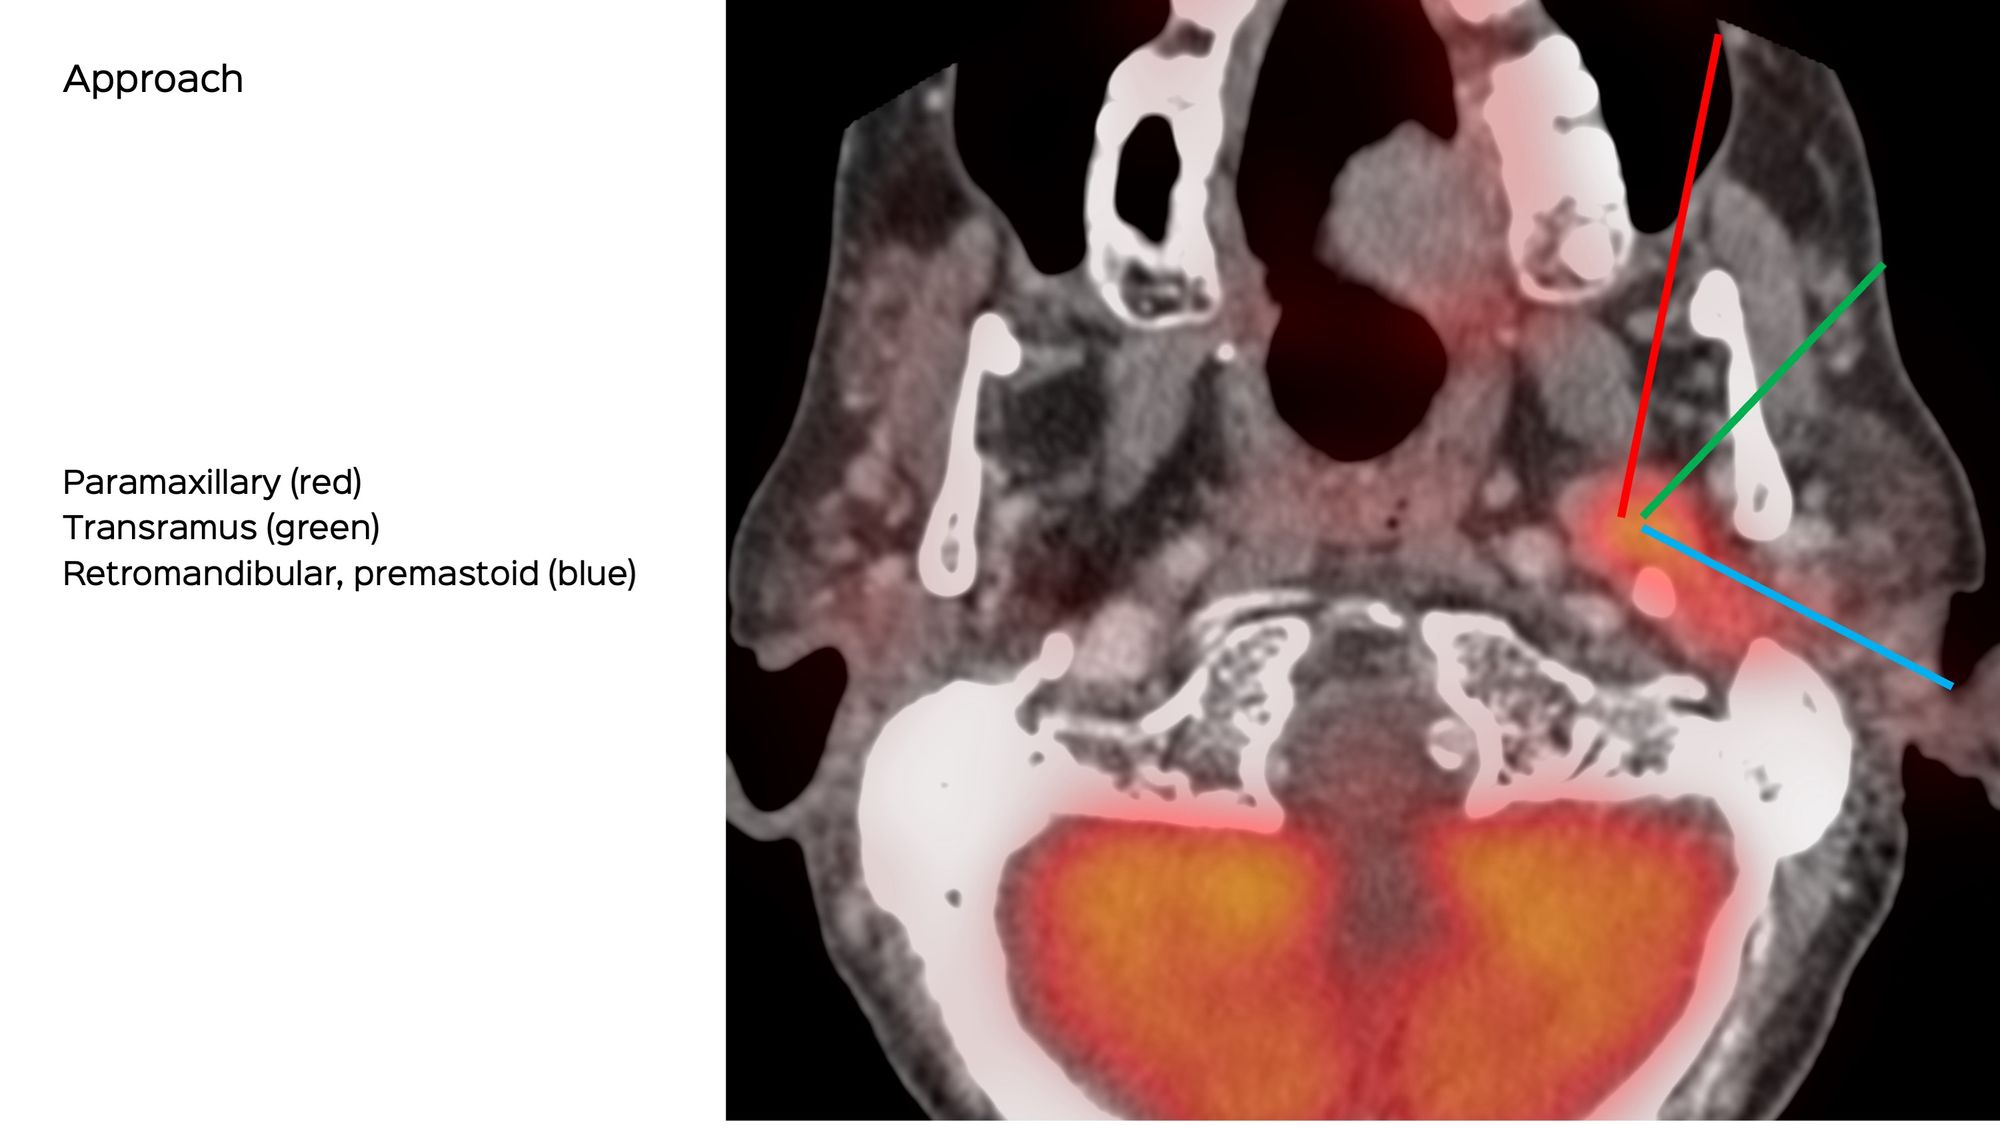

What route will you take?